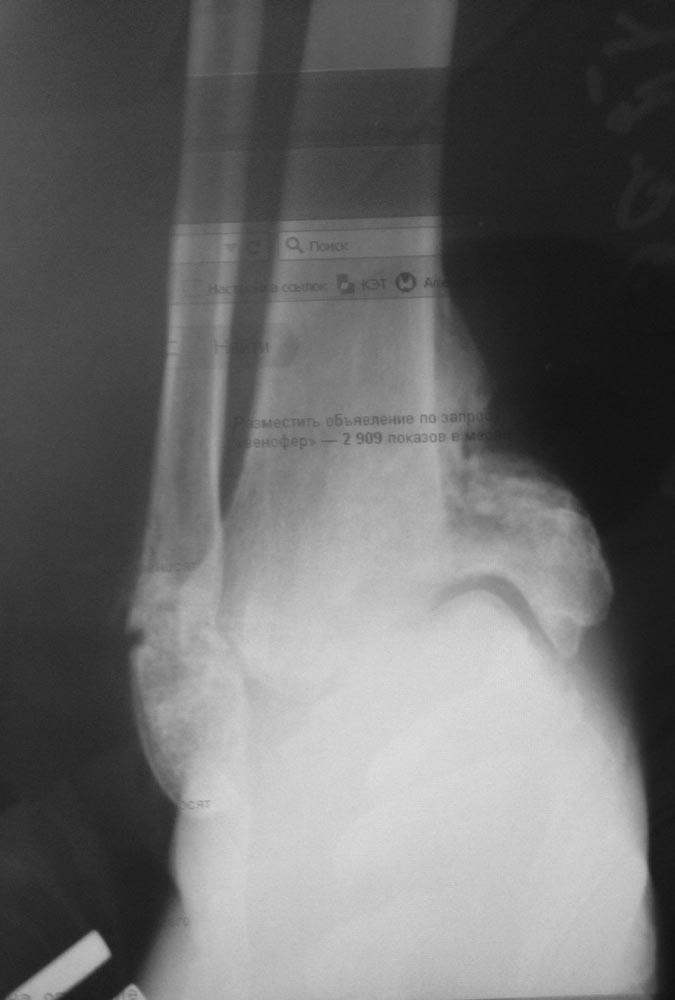

У пациентки 28 лет СД 1 типа, остеоартропатия стопы, полинейропатия.

Перелом лодыжек и пяточной кости произошёл, по-видимому, спонтанно, без

явной травмы3 месяца назад.

Сейчас признаки консолидации лодыжек в порочном положении - вн. лодыжка

смещена краниально, стопа в варусе. Аваскулярный некроз таранной кости с

частичным остеолизом.Возникает мысль о необходимости артродеза

голеностопного и подтаранного суставов штифтом.В настоящее время СД

компенсирован.